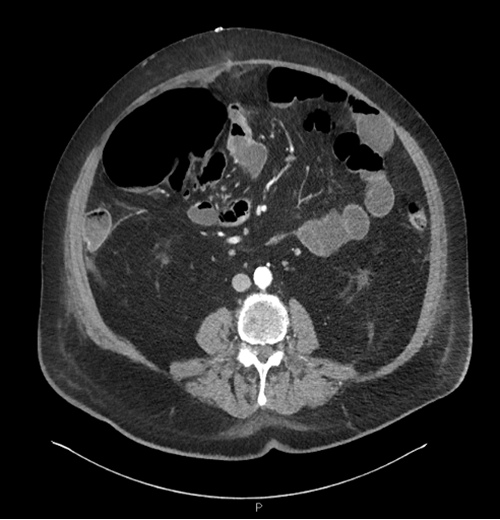

On postoperative day 1, the patient had some abdominal distention but was passing some flatus and felt well overall. On postoperative day 2, he continued to have some distention, and radiographs were obtained for a suspected ileus in the afternoon. The X ray showed multiple dilated loops of the bowel with air-fluid levels, the largest a prominent cecum measuring eight cm in the right hemiabdomen. He was made NPO, and a nasogastric tube was placed for decompression. A follow-up X ray in the evening showed an increase in the dilation of the bowel, with the cecum now measuring eleven cm. On the morning of postoperative day 3, the patient’s distention had improved after the NG placement, but on physical exam, he had focal right-sided peritonitis. A CT of the abdomen and pelvis was obtained to evaluate the cause of the obstruction, and it showed a dilated cecum measuring 8 cm that was rotated anteromedially with a small amount of free fluid present anterior to the cecum. Multiple fluid-filled loops of the small bowel were present proximal to the surgical anastomosis with several air-fluid levels. The anastomosis appeared patent, and distal to it was decompressed loops of the bowel.

With these radiologic and physical exam findings, it was recommended that the patient undergo surgery; he was taken to the operating room that day. His previous midline incision was re-opened and extended. The cecum was easily identified and found to be rotated anteriorly over the ascending colon. The cecum was distended with signs of ischemia and several serosal tears but no gross spillage. A right hemicolectomy was performed next with a stapled ileocolic anastomosis. The small bowel was run from the ileocecal valve to the ligament of Treitz. The previous anastomosis was found approximately one hundred and 10 cm from the ileocecal valve and was intact. Of note, multiple other diverticula distal to the original area of resection did not appear inflamed. The patient’s abdominal fascia was re-closed, the skin edges were left open, and the wound packed. The patient tolerated the surgery well and returned to the ward. Postop, his ileus was managed with bowel rest and NG decompression. It gradually resolved, and he was restarted on a diet. He was discharged to an acute rehab facility on hospital day 15. The patient followed up in the clinic two weeks after discharge and was doing very well. He had no pain, was tolerating a regular diet, and had normal bowel function. Since then, a review of his medical chart has not identified any further issues.

Figure 3. CT on POD3 With Dilated Cecum Measuring 11 cm in Diameter and Rotated Anteromedially. Published With Permission